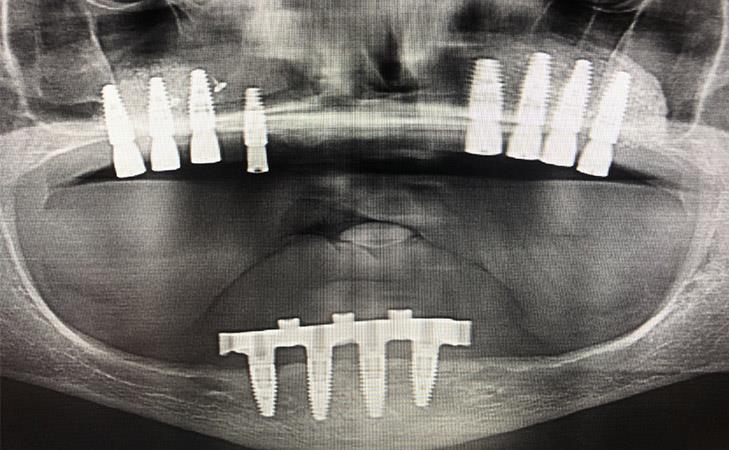

Patient has been missing all her upper teeth and has worn an upper denture for the past 20+ years. The patient underwent Bilateral Sinus Lift surgery and Bone regeneration.

44 year old male missing right and left upper teeth for years decided to have implants placed to replace his upper denture. CT scan determined there was advanced bone loss in the upper jaw under his sinus cavities. Bilateral Sinus Lift Bone Graft was performed for implant placement.